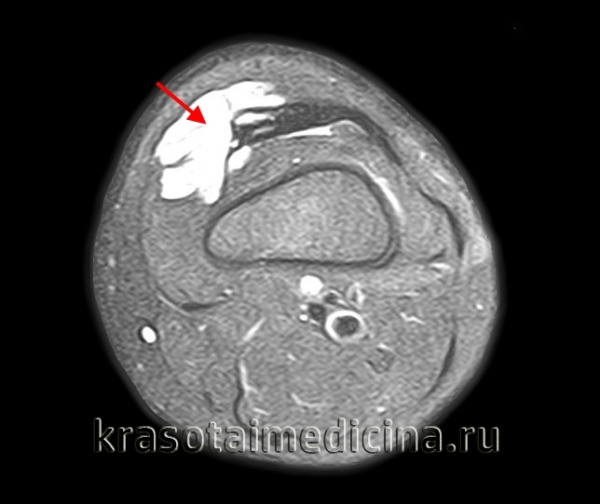

5. УЗИ при лимфангиоме:

• Однокамерное или многокамерное кистозное образование с ретроградным акустическим усилением

• Анэхогенные или гипоэхогенные кистозные пространства, зависящие от детрита в жидкости